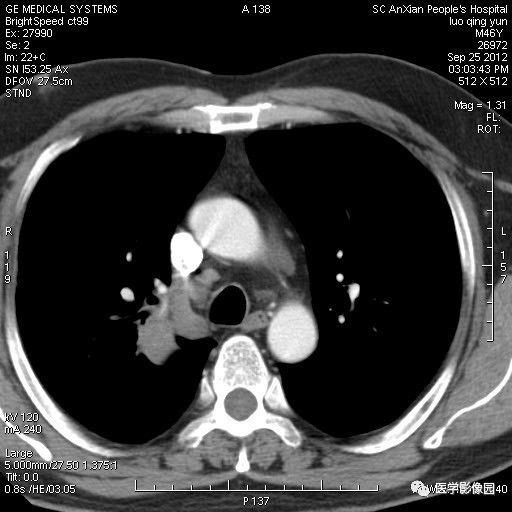

影像学表现:右上肺见不规则团块状高密度阴影,略有分叶级毛刺,边缘模糊,邻近胸膜增厚,增强扫描呈轻中度强化。

诊断结果:右上肺炎性假瘤

本病影像学表现无绝对特征性。单发多见,多位于肺表浅部位,多呈圆形或椭圆形,直径多在2-5cm或更大;多有假包膜,边缘多清晰光整,有时也毛糙,并可有分叶或毛刺;邻近胸膜局限性增厚、牵拉,病灶边缘呈桃尖样突起即桃尖征(尖端指向胸膜);增强扫描多呈中度均匀强化,持续时间较长。亦可显著强化。